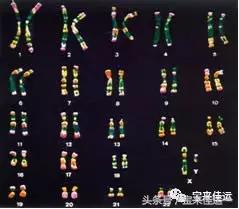

染色体是细胞核中载有遗传信息的物质,人类的性染色体是23对染色体的其中一对组成,拥有X和Y染色体各一个的个体是男性,拥有一对X染色体的个体是女性。

染色体检查是试管婴儿术前检查的主要项目,尤其是高龄女性更有检查的必要。我们都知道高龄女性怀孕有一定风险,体内卵子中染色体异常率高会导致不孕不育,试管婴儿技术实施之前,必须要经过染色体检查,确定可以进行试管婴儿手术后,才会进入试管周期。

染色体检查可以检测妇女卵细胞中携带人类遗传密码的染色体的缺陷。卵细胞染色体数目错误可能会导致胚胎流产,或导致唐氏综合征之类的严重婴儿病症。

年轻妇女多达一半的卵细胞以及年纪39岁以上妇女75%的卵细胞会有染色体异常现象,在胚胎植入子宫前对其进行染色体分析,只移植染色体正常的胚胎,能够有效提高试管婴儿的成功率,降低流产率,帮助遗传高风险的家庭生育健康的宝宝,避免出生遗传异常婴儿,降低人群中出生缺陷。